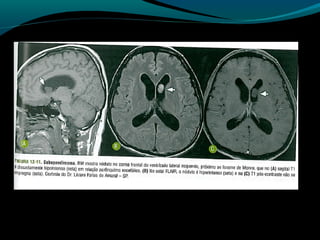

Astrocitoma subependimário de

células gigantes

Raro,

Circunscrito;

Benigno;

De crescimento lento;

Associação com esclerose tuberosa!

Faixa etária;

Localização;

Hidrocefalia;

Sintomas;

Achados histológicos:

Grau I;

Astrócitos ganglióides largos;

Pode apresentar características de astrocitoma de alto

grau;

TC:

Próximo ao forame de Monro (mas existe localização

atípica);

Expansiva e >1,5cm;

Iso ou hipodensa; pode ser heterogênea e apresentar

calcificações;

Realce intenso pelo contraste;

Suspeitar de tumor quando:

Em pacienetes com esclerose tuberosa, nódulo aumento

de tamanho e tem maior realce em exames seriados;

RM:

Baixo sinal em T1;

Alto sinal em FLAIR e T2 (ou heterogêneo se

hemorragia ou calcificações);

Regra: realce intenso e difuso pelo Gd;

RM:

Geralmente sem disseminação pelo LCR;

Aumento de Co/Cr

Redução de NAA/Cr

Picos de lactato;

Aumento da perfusão;

Paciente com CET RM

Se suspeita: controle anual por RM:

Crescimento e/ou aumento do realce de lesão próxima

ao forame de Monro  neoplasia;